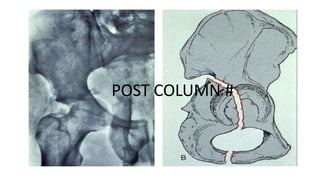

This document discusses different types of acetabular fractures including transverse, T-shaped, and both-column fractures. Transverse fractures are classified as transtectal, juxtatectal, or infratectal based on their location through the acetabular dome or fossa. Transtectal fractures require anatomical reduction while infratectal fractures may not need surgery depending on the pattern. T-shaped fractures disrupt the obturator ring and iliopectineal and ilioischial lines but do not involve the iliac wing, differentiating them from both-column fractures. CT scans can further classify fractures in the coronal or sagittal planes.